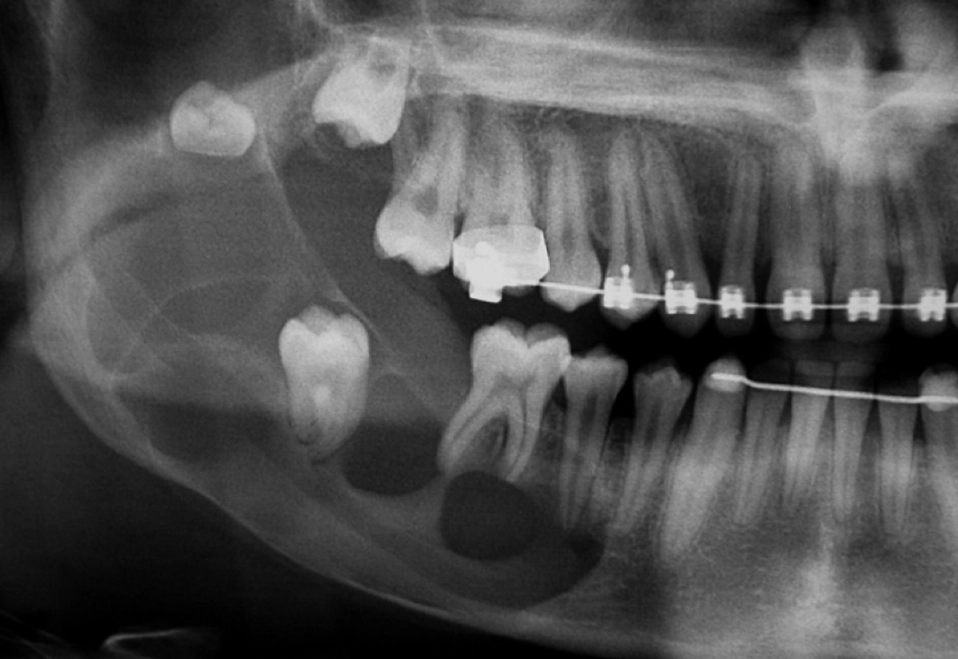

2. Cone Beam Computed Tomography (CBCT): If the cyst looks large or complex on the OPG, a 3D CBCT scan is the gold standard next step. This shows the exact size, shape, and relationship of the cyst to critical structures like nerves, sinuses, and adjacent tooth roots in three dimensions. It's essential for surgical planning.

A common mistake I see is dentists planning surgery based solely on a 2D X-ray. Without a 3D scan, you're essentially navigating in the dark. You might not know the cyst is wrapped around the nerve until you're in the middle of the procedure, which increases the risk of nerve injury.